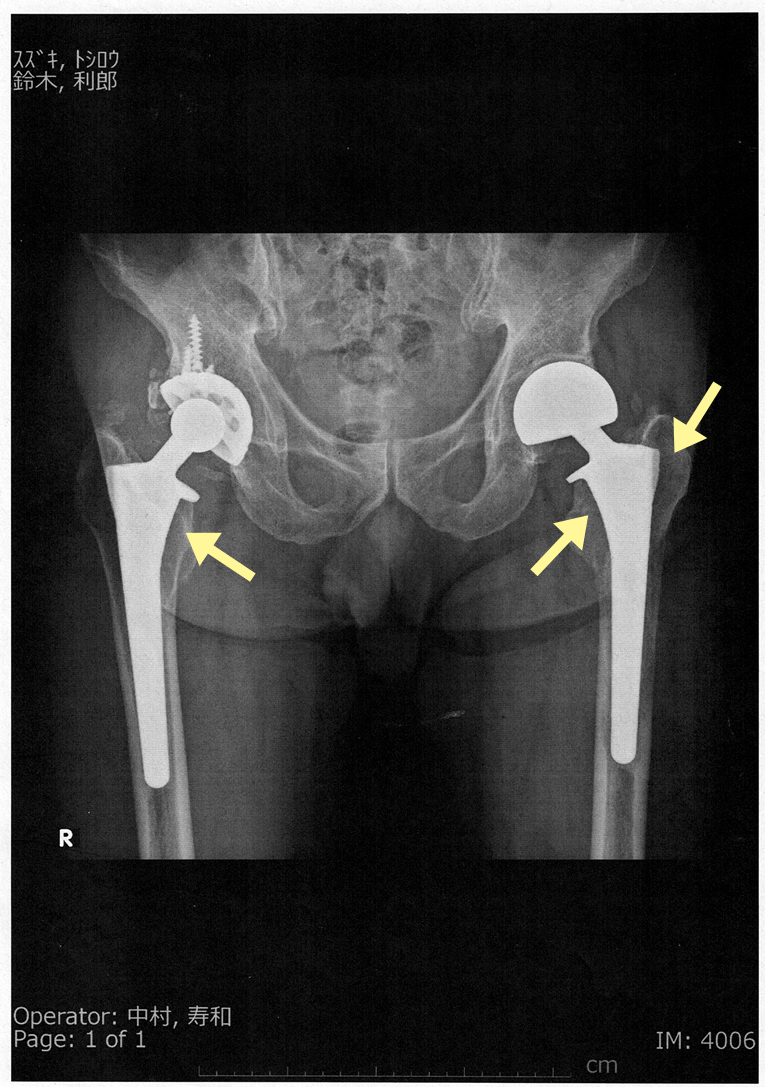

左脚に前立腺がんが転移して、骨が溶けてる状態になってるわけだが、この段階ではそうは見えない。

撮影角度によるのか、専門家が見るとわかるのか。

このCTスキャンで骨格が明確に観察され、左脚の大腿骨が斜めに骨折しているのがわかる。

前立腺がんが大腿骨に転移していたのだ。

観血的整復固定術、

後からパスを見たら、「左大腿骨近位端病的骨折」

私の場合、人工骨頭なので若干異なり、チタン合金製の人工骨頭を大腿骨の中にスポット入れたわけで、その大腿骨の上部に前立腺がんが転移し、そこが骨折したわけである。